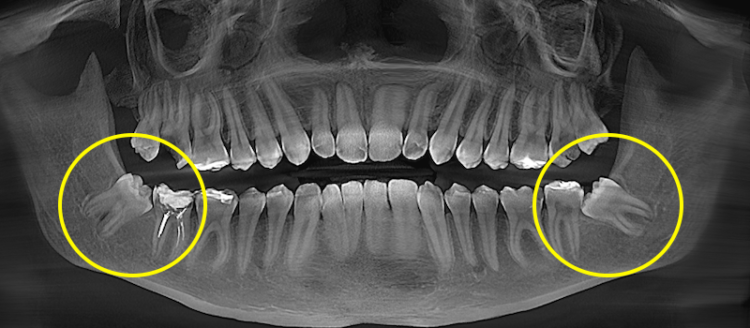

Просте й складне видалення зуба

Складність визначається не розміром зуба мудрості, а його положенням у кістці, напрямком росту, формою коренів та близькістю до анатомічних структур (нижньощелепний нерв, гайморові пазухи). Перед втручанням ці параметри оцінюються клінічно та на рентгені або КТ, що дозволяє спрогнозувати обсяг операції.

Зуб мудрості частково або повністю розташований у кістці (ретинований) або має неправильний напрямок росту (дистопований). Коронка може бути перекрита кісткою, а корені — близько до нерва або мати складну форму.

Дистопований зуб мудрості — це зуб, який прорізався або частково прорізався, але займає неправильне положення в зубному ряду. Найчастіше він нахилений у бік 7-го зуба, росте під кутом або зміщений у бік щоки чи язика.